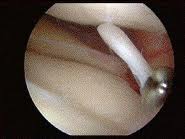

Вот такие изображения можно наблюдать во время артроскопии колена :

Сустав промывают, извлекают разрушенные фрагменты хряща, менисков, удаляют остеофиты. Эта операция паллиативная, но она при малой травматичности позволяет улучшить функцию сустава на 2-3 года. Если обнаруживается преимущественное поражение внутренней или наружной части сустава, при небольших искривлениях голени, возможно выполнение операции под названием корригирующая вальгизирующая подмыщелковая остеотомия большеберцовой кости при поражении внутреннего отдела коленного сустава.